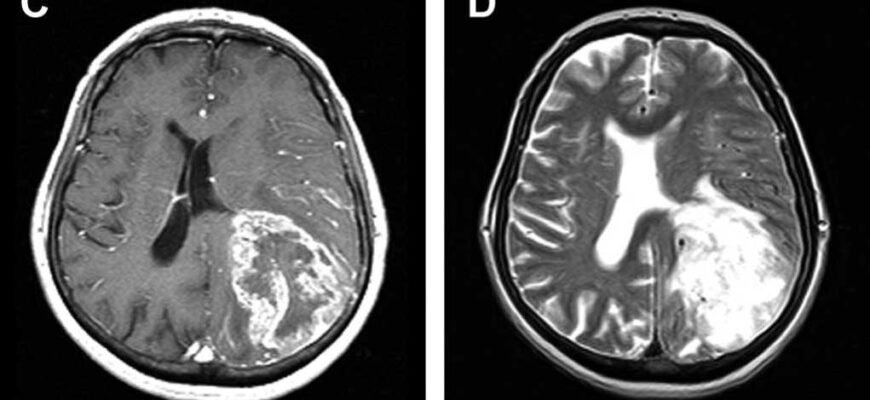

Якщо у вас є підозри щодо набряку головного мозку, негайно потрібно проконсультуватися з лікарем. Діагностика цього стану включає:

- Комп’ютерну томографію (КТ) голови.

- Магнітно-резонансну томографію (МРТ).